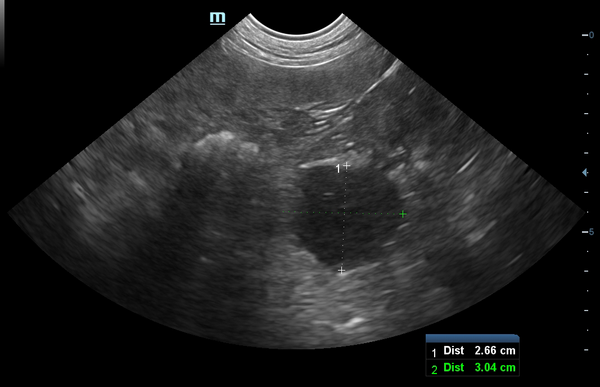

Tiger ist inzwischen ein 17-jähriger Europäisch-Kurzhaar-Kater. Letztes Jahr wurde er uns im Sommer wegen chronischer Magen-Darm-Beschwerden und Gewichtsverlusts vorgestellt. Trotz seines Alters scheuten seine Besitzer keine Kosten und Mühen. Im Ultraschall zeigten sich eine verdickte Darmwände, besonders die Muskelschicht war sehr dick (rote Markierung). Um der Ursache auf den Grund zu gehen, entnahmen wir Gewebeproben. Von dem Eingriff erholte sich Tiger sehr gut und die Wunden heilten ab.

Im Ultraschall ist deutlich zu sehen, dass die Darmwand nicht mehr verdickt und der Tumor unter Therapie derzeit unter Kontrolle ist.